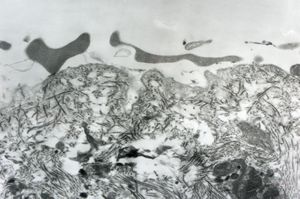

M, 3y. | lipofuscinosis

M, 3y. | lipofuscinosis

M, 3y. | lipofuscinosis